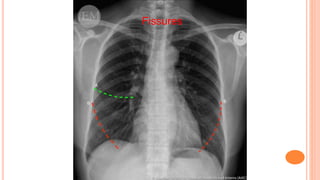

Fissures

• #33 So you should compare the lung parenchyma left to right in the upper, middle and lower zones and see whether there is a difference. Look for equal radiolucency between the left and the right lungs zones. The horizontal fissure on the right divides the upper and middle lobes; from the hilum to the 6th rib at the axillary line. You should also check soft tissues outside the thorax for subcutaneous air, foreign body, bizarre density, etc.